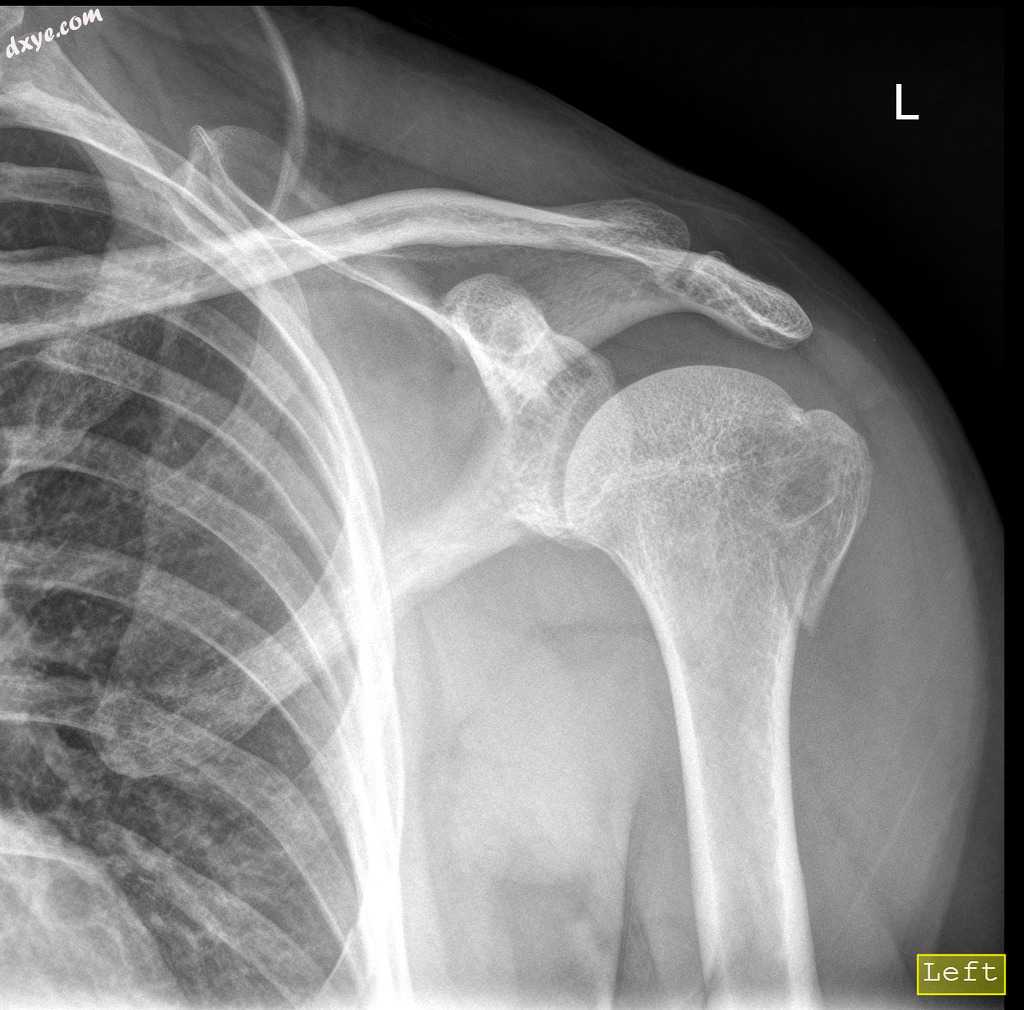

肱骨大结节骨折

跌倒,左肩压痛,肩部运动受限引起的左肩创伤史。

年龄:50岁

性别:男

正位

左肱骨大结节骨折。

未见脱位。

肱骨大结节是三块肌肉连接的地方,所以这里的骨折限制了肩关节的稳定性和运动。

这种骨折通常发生在外伤、车祸、跌倒和肩关节脱臼。

这个病人接受保守治疗。